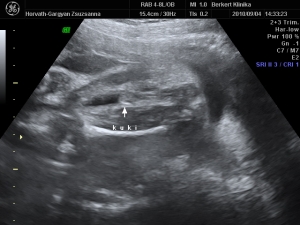

Nagyon aranyos a pocakod!